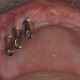

Der zahnlose Unterkiefer ist eine der ältesten und sichersten Indikationen für Implantate. Eine konventionelle Totalprothese ist meist eine unbefriedigende Lösung für den Patienten, zudem bedeutet sie eine erhebliche Einbuße an Lebensqualität. Der Grund dafür ist leicht nachzuvollziehen. Der liebe Gott hat es nicht so vorgesehen, dass eine Prothese auf der Schleimhaut aufliegt, denn selten kann die Prothesenbasis die Prothese stabil lagern - es kommt zu schmerzhaften Druckstellen und zudem mit der Zeit zu einem immer geringer werdenden Halt der Prothese durch den zwangsläufigen Knochenabbau. Oftmals der Beginn eines Teufelskreises. Auch wenn komplette Zahnlosigkeit vorliegt, kann mit Implantaten wieder ein fester Biss wie mit den eigenen Zähnen erreicht werden.

Mit Hilfe von Implantaten können Verankerungselemente, wie beispielsweise Magnete, Kugelköpfe, Teleskope, Stege, für einen sicheren Halt für den Zahnersatz sorgen. Bei bestimmten Voraussetzungen kann sogar ein absolut festsitzender, also nicht herausnehmbarer Zahnersatz realisiert werden.

Die einfachste Versorgung ist mit zwei Implantaten möglich, wobei für den zahnlosen Unterkiefer vier Implantate als Standard empfohlen werden und für den zahnlosen Oberkiefer sechs. Es ist leicht nachvollziehbar, dass sich mit steigender Implantatzahl die Stabilität des Zahnersatzes erhöht.